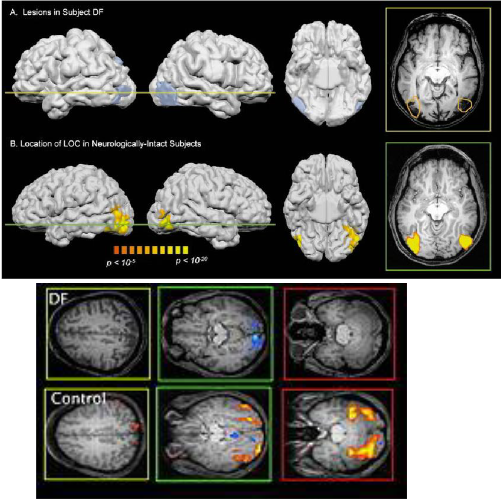

Apperceptive agnosia

you can perceive an object's individual features, but you can't bind them together.

Can perceive an objects features but not the object in entirety

Ex: patient D.F, drawing a ladel,

Sometimes people can infer based on their knowledge to make conclusions , but they cannot perceive these things as intact objects

Cannot solve their own binding problem

Patient DF: had bilateral lesions in …

the occipital cortex